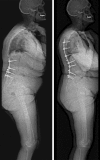

Material and method: The authors proposed their method for the osteotomy planning paying attention to the pelvic, and spine parameters and in accordance with Roussouly's classification. The pre operative planning is based on a full-body X-ray including the spine from C1 to the femoral head and the first 10 cm of the femur shaft. Using all the balance parameters provided, a formula name FBI is proposed. Calculation of the osteotomy is basic goniometry, the midpoint of the C7 inferior plateau (point a) is transposed horizontally on the projected future C7 plumb line (point b) crossing posterior S1 plateau on a sagittal X-ray. These are the first two reference points. A third reference point is made on the anterior wall of the selected vertebra for osteotomy at mid height of the pedicle (point c) mainly L4 vertebra. These three points form a triangle with the tip being the third reference point. The angle represented by this triangle is the theoretical angle of the osteotomy. Two more angles should be measured and eventually added. The femur angulation measured as the inclination of the femoral axis to the vertical. And a third angle named the compensatory pelvic tilt to integrate the type of pelvis. If the pelvic tilt is between 15 and 25° or is higher than 25° you must add 5 or 10°, respectively. This compensatory tilt is based on a clinical analysis of operated patients.

Results: This planification was applied in a retrospective study of 18 patients and showed why in some cases improper correction was performed and prospectively in 8 cases with good clinical outcomes and correct spinal alignment. Sometimes it is necessary to find an acceptable compromise when rebalancing the spine paying attention to the general parameters of the patients like: age, osteoporosis, systemic disease etc.